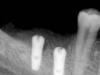

carloss Опубликовано 23 февраля, 2013 Автор Поделиться Опубликовано 23 февраля, 2013 (изменено) Присоединяюсь к вопросу про бор.Сегодня пытался расщипиться в обл 45 и 46. Работу завалил по неумению. По КТ- ширина гребня в обл 45 и 46 около 4.5 мм, до канала 12 и 11 мм соответственно. Гребень хороший-покатый. Пропил по гребню делал борами NTI 1, 4 мм в диаметре, длина рабочей части 8 мм, длина хвостовика XL, под физик.На пропиле по гребню , как только столкнулся с межкорневой перегородкой (после удаления 3 мес), сьехал бор вестибулярно, вертикальные пропилы без проблем. Далее пилотником из набора МИС начальные ложе под имплантаты, потом конвекс остеотомы МИС по размерам постепенно, оставляя один из них в ложе. На вкручивании остеотома в 3 мм, затрещала кортикалка вестибулярно у 46. В конце концов имплантаты 3.6 мм в диам и 10 длиной закрутил, в обл 46 - 3 мм вестибулярно винт не в кости,Собственно расщипления не получил. Графт -- ксено+ ауто, мембрана в два слоя. Чего там дальше будет отпишусь. Хорошо бы увидеть срез КТ.. Если область двух зубов, то диск Кури туда спокойно подлазит, стенки толще останутся.. Или фрезой, меньше меньше 1 мм.. В области недавно удалённых зубов сои особенности, как правило кость бывухает вестибулярно в области остеотома, как тут Это старая работа, щас бы сделал несколько иначе, но все таки http://s018.radikal.ru/i503/1302/fe/2315f1544fab.jpg http://s017.radikal.ru/i420/1302/81/e17c7167af12.jpg http://s001.radikal.ru/i193/1302/0f/3b4cf255649c.jpg дальше все по протоколу)) http://s017.radikal.ru/i430/1302/2d/484266b54425.jpg http://s005.radikal.ru/i210/1302/8b/f594fda80c66.jpg http://s002.radikal.ru/i200/1302/9b/de70472e71c8.jpg http://s16.radikal.ru/i191/1302/56/756f6e2152eb.jpg ну может это тут случай, когда стоит воспользовать тонким долотом, для начального отведения вестибулярной стенки целиком.. Когда начинаете раширять остетомом, то чувствуется, насколько кость расщеляема.. иногда останавливаюсь и увеличиваю длину вестибулярных распилов.. и лучше трапецевидная форма вестибулярной костной стенки, основанием вниз.. так вероятность перелома меньше, хотя не всегда оно возможно Изменено 23 февраля, 2013 пользователем carloss 5 Ссылка на комментарий

carloss Опубликовано 23 февраля, 2013 Автор Поделиться Опубликовано 23 февраля, 2013 Вот ещё случай, когда классического расщепления не получилось, тоже старый, думаю сейчас бы побольше отвел стенки.. но в целом на прогноз это не повлияло.. шейки в нативной кости, пусть и потрескавшейся http://s51.radikal.ru/i134/1302/d1/6607aaa038f0.jpg 1 Ссылка на комментарий